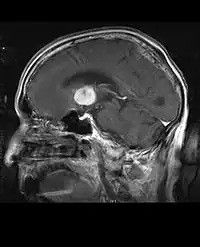

Computertomografi (CT) og magnetisk resonansbilleddannelse (MRI) kan effektivt påvise en neoplasi i hjernen. MR er mere følsom end CT til at identificere læsioner, men har kontraindikationer for patienter med pacemakere, inkompatible proteser, metalclips og andre. CT er fortsat den foretrukne metode til at påvise forkalkninger i læsioner eller knogleerosion af kaloten eller bunden . Brugen af kontrastmidler, som er ioderede i tilfælde af CT og paramagnetiske (gadolinium ) i tilfælde af MR, tillader erhvervelse af information om vaskularisering og integritet af blod-hjerne-barrieren, en bedre definition af den tumorøse tumor sammenlignet til det omgivende ødem og generering af hypoteser om graden af malignitet . Den radiologiske undersøgelse giver også mulighed for en vurdering af de mekaniske virkninger og deraf følgende ændringer i hjernestrukturer som følge af tumoren, såsom hydrocephalus og brok, hvis virkninger kan være dødelige. Til sidst, som forberedelse til operation, kan denne diagnostik bruges til at bestemme placeringen af læsionen eller infiltrationen af tumoren i vitale områder af hjernen. Til dette formål er MR mere effektiv end CT, fordi den kan give tredimensionelle billeder.

På-MRI viser en intrakraniel tumor som en massiv læsion, der kan blive mere selvlysende efter brug af kontrastmidlet. Der er dog altid en signalanomali i-Magnetisk resonansbilleddannelse, som indikerer tilstedeværelsen af neoplasi eller vasogent ødem. Sædvanligvis er øget luminescens (kontrastforbedring) tegn på en tumor af en højere grad af malignitet. En kontrastring er karakteristisk for glioblastom, hvor den selvlysende del svarer til den vitale del af den ondartede tumor, og den mørkere del-hypointense område svarende til vævsnekrose.